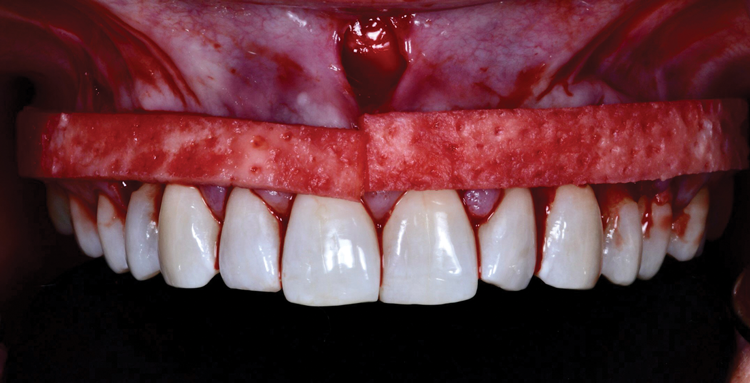

(6.) Preoperative retracted view of the generalized gingival recession in the maxilla extending from tooth No. 4 through tooth No. 13.

Figure 6

A female patient presented to the practice with generalized gingival recession in the maxilla that extended from tooth No. 4 to tooth No. 13 (her maxillary first premolars were missing). The recession was classified as Cairo RT1 for all affected teeth, and the root exposure ranged from 1 mm to 4 mm. As part of the examination, radiographs were acquired; however, no remarkable interproximal bone loss was observed (Figure 5). Teeth Nos. 4, 6, 10, 11, and 13 were the most severely affected, and NCCLs were present on the canines and premolars (Figure 6). More specifically, tooth No. 4 presented with 3 mm of recession and an NCCL; tooth No. 6 presented with 3 mm of recession and an NCCL; teeth Nos. 7 through 9 presented with 1 mm of recession and no NCCLs; tooth No. 10 presented with 4 mm of recession and an NCCL; tooth No. 11 presented with 4 mm of recession and an NCCL; and finally, tooth No. 13 presented with 3 mm of recession and an NCCL. All of the NCCLs demonstrated a Winter and Allen classification of NCL3. The patient's keratinized tissue was greater than 2 mm for all teeth, her periodontal phenotype was thick, and her midline frenum was prominent and inserted 5 mm apical to the tip of the papilla between teeth Nos. 8 and 9.